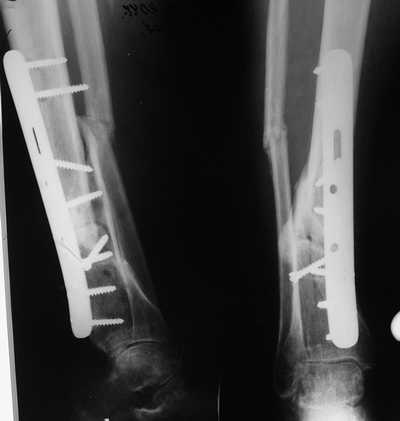

остеотомия м\б кости, аппарат Илизарова. По рентгенограммам в двух проекциях

произведено планирование устранения смещений (рис 2 и 3), между вторым и

третьим кольцом установлены 6 телескопических дистракторов Гесапода, данные

введены в программу, и далее втечение 10 дней больная подкручивала телескопы

согласно выданной компьютером инструкции. По завершению репозиции

гексаподные телескопы обратно заменены на обычные штанги от аппарата

Илизарова (рис 4 и 5). Еще через две недели забит гвоздь (рис 6, контроль